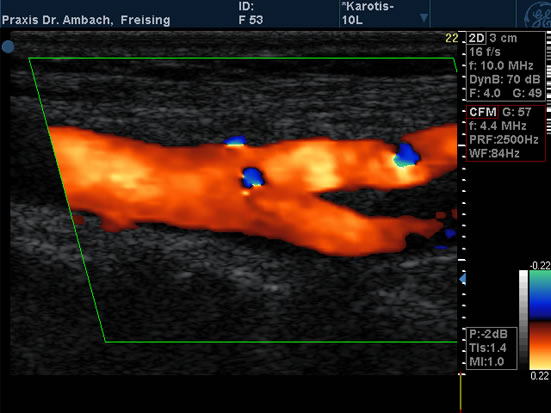

Gefäßdoppler

Gefäßdoppler - 2